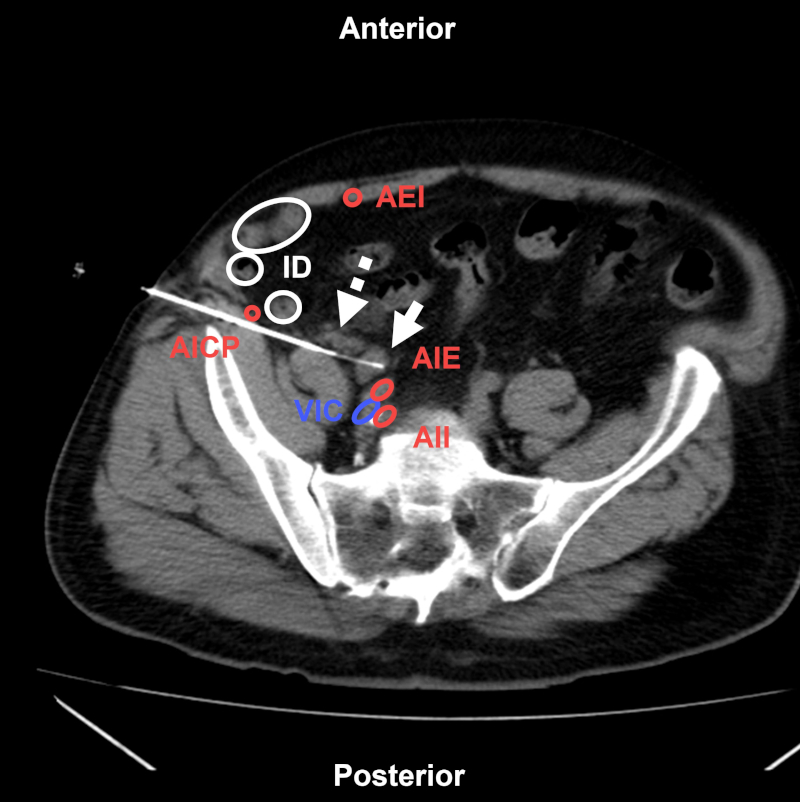

Los accesos para BP pueden ser por vía anterior, lateral o posterior. El abordaje transabdominal anterior (Fig. 17) o lateral (Fig. 18) es útil para alcanzar lesiones ubicadas a nivel paravesical, cadenas ilíacas comunes o imágenes mesentéricas. En caso de utilizar esta vía, se deberá evitar lesionar los vasos epigástricos inferiores, la arteria ilíaca circunfleja profunda, los vasos ilíacos y los órganos de la pelvis1,29.

Figura 18

Varón de 75 años con antecedentes de cáncer de vejiga y adenopatía en cadena ilíaca primitiva. BP coaxial transabdominal anterolateral (flecha) bajo TC, reconstrucción multiplanar. Estructuras a evitar: AICP: arteria ilíaca circunfleja profunda; AEI: arteria epigástrica inferior; AIE: arteria ilíaca externa; AII: arteria ilíaca interna; VIC: vena ilíaca común; ID: intestino delgado. Nótese el pequeño hematoma anterolateral a la adenopatía (flecha discontinua). Aguja utilizada: PL 18 G con Supercore 20 G (sistema semiautomático). Diagnóstico final: adenopatía reactiva.